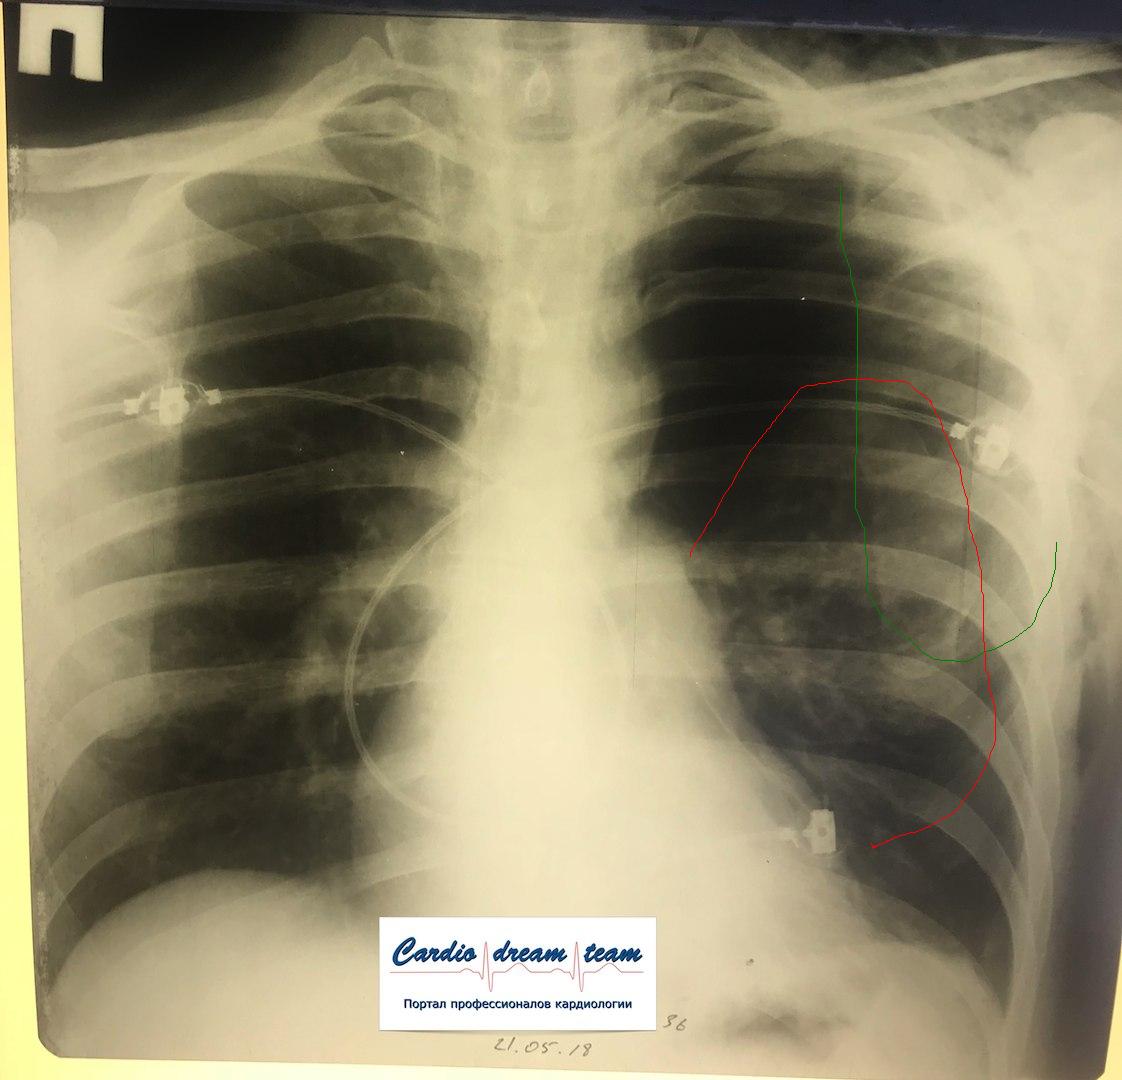

Проведена рентгенография органов грудной клетки в прямой проекции, положение полусидя, условия ПИТ, Р-контроль Легочные поля: Отрицательная динамика: правое легкое поджато к корню. Тень средостения резко смещена влево. Выраженная подкожная эмфизема мягких тканей грудной клетки справа. Тень подключичного катетера в проекции ВПВ. Легочный рисунок: диффузно деформирован за счет пневмосклероза, сгущен справа Корни: тень средостения смещена влево Синусы: нечеткие Сердце: широко лежит на диафрагме (позиционно) ЗАКЛЮЧЕНИЕ: Правосторонний пневмоторакс, отрицательная Р-динамика. Эмфизема мягких тканей грудной клетки. Пневмосклероз. Р-контроль.